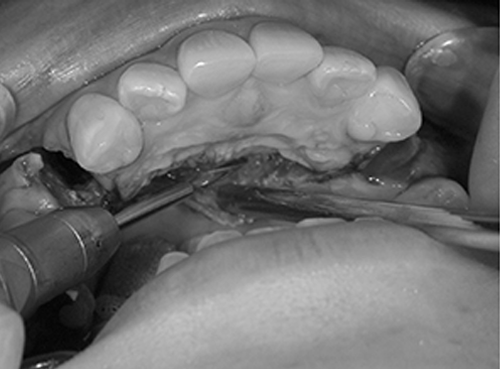

6. 骨を削ります

デザインで確認をした骨の切除範囲と骨の切離範囲に沿って骨切りをおこないます。骨切離は、骨がやけどをしない様に、生理食塩水を注水して、骨を冷やしながらエンジンやドリルで骨を切ります。

痛くありませんし、無意識の真っただ中ですから、振動も感じません。安心してください。この時に、歯の根元を傷つけないように、歯の根の先から5mm以上離します。

骨はコの字型に切ります。水平の骨切り線は、歯の根や神経を傷つけないよう、下の犬歯の根の尖端から5mm以上下方におこなっています。

下あご犬歯の根の尖端は、剥離した部分から見える骨から透けて見えることが多いので、傷つけることはありません。抜歯した歯の根の長さを参考にすることもあります。

抜歯した歯の部分の骨を削って、後ろに下げるために必要な骨のすき間を作ります。この部分の骨を削りすぎると、手術後に骨のすき間ができてしまいます。その他、骨と骨、歯と歯のすき間ができてしまう時もあります。下顎犬歯、下顎小臼歯が傾いてしまったり、部分的な歯周病になり、骨が融けてしまったり、歯が抜けてしまうこともあります。この部分の骨の削除はこの手術では、最も大切な手術のパートヤマ場と言えます。

カンファークリニックでは、模型を使用したモデルサージェリー、シミュレーション手術をおこなって、細心の準備と注意をしながら手術をおこなっています。骨を削る機械は専用のサジタルブレード(刃先)を使います。 水平的な骨切りと、垂直的な骨切りを組み合わせて、骨が後ろに下がるように骨を削り、骨を動かします。